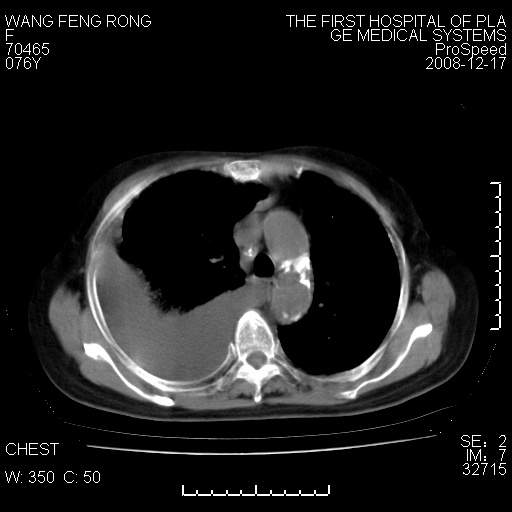

标题: CT17742:咳嗽,消瘦一月,有结果

右肺大部实变,其内可见支气管影,但分支减少,宽窄不均,走行僵直,同侧胸腔大量积液;纵隔内见多发淋巴结影,但淋巴结大部有钙化;主动脉壁钙化;临床上病人咳嗽、消瘦。所以我考虑:1、结核(依据:右下肺实变,纵隔内淋巴结符合结核表现,同侧并发胸膜炎表现);2、支气管肺泡癌(依据:实变的肺组织内支气管分支减少,宽窄不均,走行僵直,没有把它放在第一诊断是因为没有看到明显肿大的淋巴结);3、动脉硬化(主动脉壁钙化就支持这个诊断)。

病理结果,肺泡癌